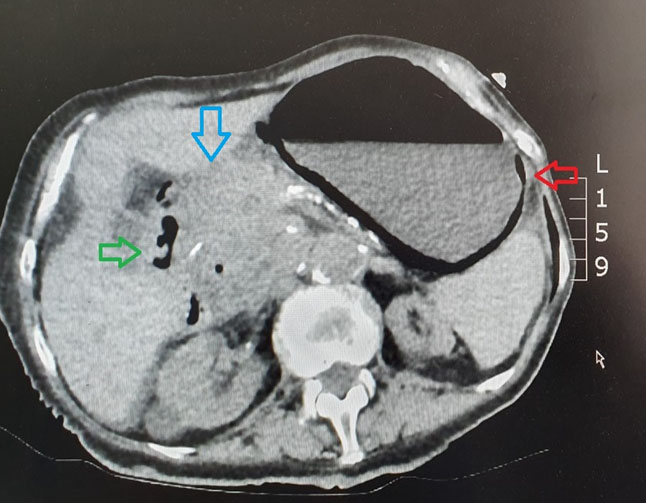

She had a CT abdomen pelvis that was noncontrasted scan due to her deteriorating renal function which revealed intramural gas within stomach wall and small amount of gas extramurally with pneumobilia likely from recent ERCP (Figure 2 and Figure 3). There was also a large mass identified at porta hepatis, however, due to the noncontrasted scan, the clear origin where the mass was arising from was not distinctly identified.

Figure 2: Axial noncontrast CT scan. Red arrow: intramural gas within gastric wall; Green arrow: porta venous gas on CT scan; Blue arrow: large mass identified at porta hepatis.